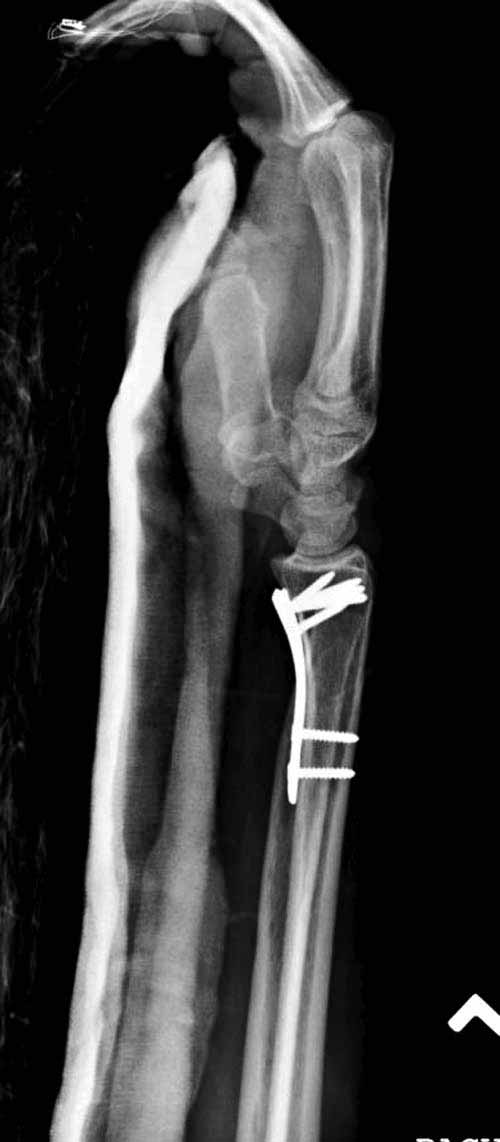

Сегодня все компании: Synthes, Stryker, Zimmer, Acumed, TriMed и т.д. имеют пластины для фиксации дистального перелома лучевой кости. На снимке метод фиксации дистальных переломов, справа Stryker, а слева пластина Synthes,

женщина 58 лет, политравма.